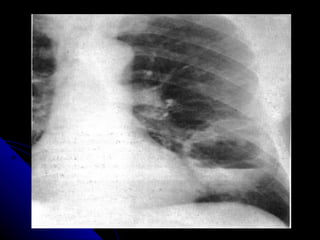

RADIOLOGIA Los infiltrados pueden ser muy pequeños y difíciles de apreciar especialmente en radiografías portátiles. La pausa inspiratoria es prácticamente imposible cuando el paciente se encuentra en ventilación mecánica haciéndolas menos específicas para el diagnóstico. La Tomografía Axial del tórax puede diagnosticar hasta en un 26% más, infiltrados pulmonares a más de definirlos más exactamente que la placa simple del tórax

RADIOLOGIA Los infiltradospueden ser muy pequeños y difíciles de apreciar especialmente en radiografías portátiles. La pausa inspiratoria es prácticamente imposible cuando el paciente se encuentra en ventilación mecánica haciéndolas menos específicas para el diagnóstico. La Tomografía Axial del tórax puede diagnosticar hasta en un 26% más, infiltrados pulmonares a más de definirlos más exactamente que la placa simple del tórax